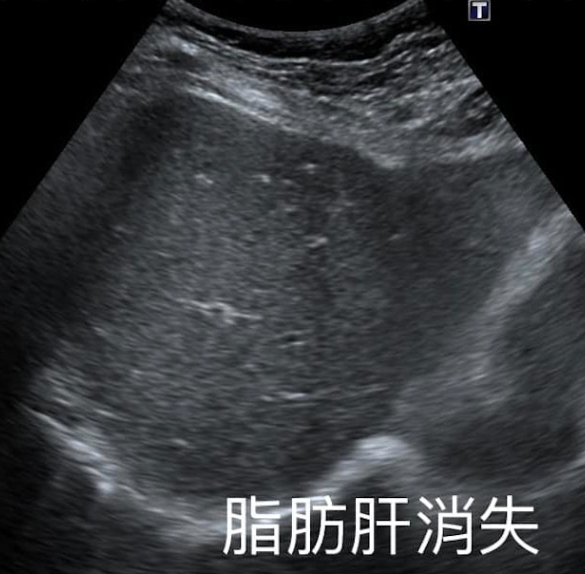

复诊时,医生发时妇人的脂肪肝已经消失。从超声波可见,脂肪消失后肝脏就恢复深色。

患者是1名60多岁女士,患有长期高血压及脂肪肝,于去年检查时仍属于中度脂肪肝,体重为66公斤。但近日复诊B超时,医生发现她肝脏完全正常,脂肪消失了,更惊讶发现她在1年内成功减重约10公斤。